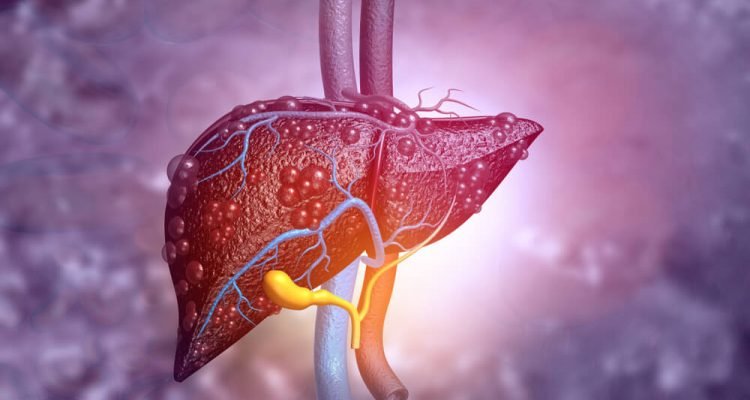

Kepenys yra svarbiausias organas, atsakingas už organizmo detoksikaciją. Per jas filtruojami visi į žmogaus organizmą patenkantys toksinai. Tačiau yra gėrimų, galinčių sutrikdyti jų veiklą ir pakenkti bendrai sveikatai.

Ne paslaptis, kad alkoholis turi didžiausią neigiamą poveikį kepenims iš visų galimų gėrimų. Alkoholis gali sukelti kepenų cirozę, kai kepenų audiniuose atsiranda randų, kurie trukdo joms tinkamai funkcionuoti. Jei ši liga negydoma arba neatliekama transplantacija, kepenų ciroze sergantis žmogus gali mirti.

Be abejonės, tokios diagnozės negalima nustatyti po vienos taurės vyno ar po vieno linksmybių vakaro. Labiausiai neproblemiškas yra kaupiamasis poveikis, kuris atsiranda dažnai vartojant alkoholį. Be alkoholinės riebalinės ligos ir cirozės, galima susirgti hepatitu. Visos šios ligos gali būti mirtinos. Nesaugus alkoholio kiekis yra 15 ir daugiau gėrimų per savaitę vyrams ir 8 ir daugiau moterims per tą patį laikotarpį, teigia Ligų kontrolės ir prevencijos centro gydytojai.